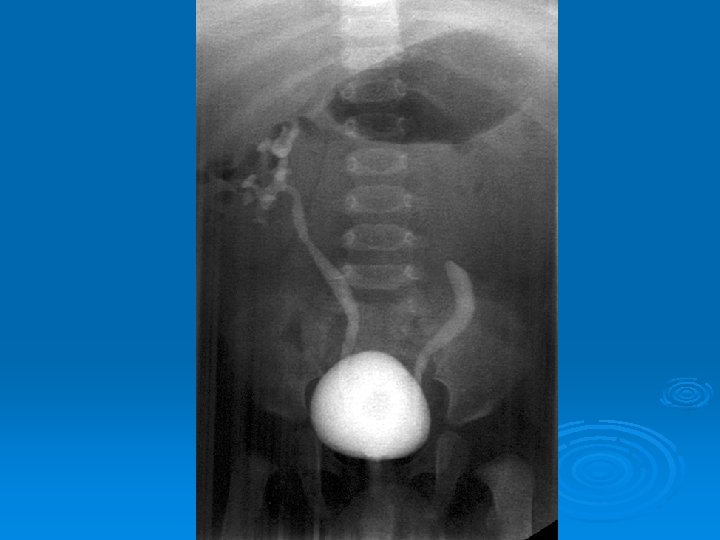

Çocukluk Çağında İdrar Yolu Enfeksiyonları İZLEMDE TANISAL GÖRÜNTÜLEME YÖNTEMLERİ Ø Miksiyon sistoüretrografisi: Vezikoüreteral geri kaçış (VÜR) görüntülenir. Ø DMSA sintigrafisi: Skar görüntülenir. Ø IVP: Tıkanıklık görüntülenir. Ø DTPA sintigrafisi: Tıkanıklık, böbrek fonksiyonları bozuk hastalarda atılım fonksiyonlarını değerlendirilebilir.